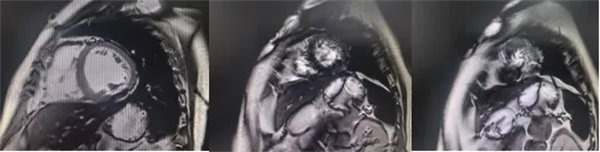

在常規(guī)心臟MRI檢查中,醫(yī)學(xué)影像科發(fā)現(xiàn)患者心肌異常表現(xiàn),考慮鐵過(guò)載性心肌病,為明確診斷要進(jìn)一步加做鐵定量技術(shù),加掃T2 mapping序列。CMR鐵定量技術(shù)是目前評(píng)估心肌鐵含量的“金標(biāo)準(zhǔn)”,能夠快速、無(wú)創(chuàng)、精準(zhǔn)量化心肌內(nèi)鐵沉積程度,檢查結(jié)果提示患者局部心肌T2*值顯著低于正常范圍,符合鐵過(guò)載性心肌病的診斷標(biāo)準(zhǔn)。

基底部、中間部及心尖部 局部心肌T2*值明顯減低T2* 10-20/s, 部分小于10/s

心肌信號(hào)局部減低 呈現(xiàn)“黑色心肌”表現(xiàn),這是由于鐵沉積導(dǎo)致局部磁場(chǎng)不均勻,引起信號(hào)丟失(失相位)。